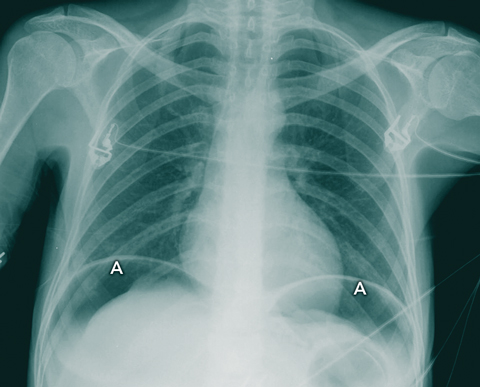

An erect chest x-ray confirmed the presence of gas under the diaphragm (Box 1). An urgent laparotomy revealed a perforated anterior gastric antrum ulcer and 2.6 L of green turbid fluid in the peritoneal cavity. The patient was given an additional four units of packed red cells intraoperatively, and her ulcer was oversewn. Postoperatively, she was transferred to an intensive care unit at another hospital.